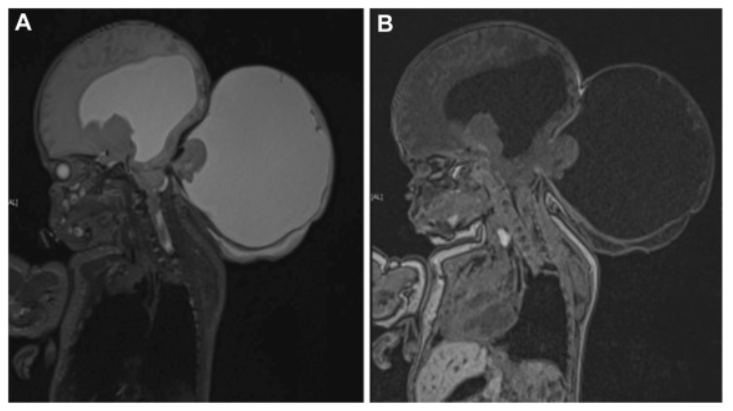

孕妇随即接受了多学科团队会诊。胎儿磁共振成像检查结果揭示,位于胎儿脑后枕部的巨大膨出物,实际上是一种被称为Chiari III型畸形的先天性结构异常。此种畸形十分罕见,且预后通常较差,患儿往往难以长期存活。即便能够幸存,其认知功能与行为发育水平也多表现较弱,大部分患儿的智力水平或神经功能会低于正常标准,可能出现智力障碍或神经功能缺陷。

是否继续妊娠?从医学角度评估,不良的预后倾向可能指向终止妊娠。然而,基于孕妇个人的宗教信仰,她最终决定将胎儿娩出。在后续的孕期检查中,脑膨出持续增大,似乎预示了这个孩子未来将面临的重重挑战。

妊娠至第九个月时,孕妇接受了剖腹产手术,婴儿顺利娩出。新生儿头围测量为34厘米,但其脑后的巨大膨出物周长竟达40厘米,尺寸甚至超过了婴儿头部。值得欣慰的是,婴儿意识状态清醒,四肢具备自主活动能力,心肺功能维持稳定。此外,进一步检查还发现了脑干下疝、颈髓空洞症以及加重的脑积水。